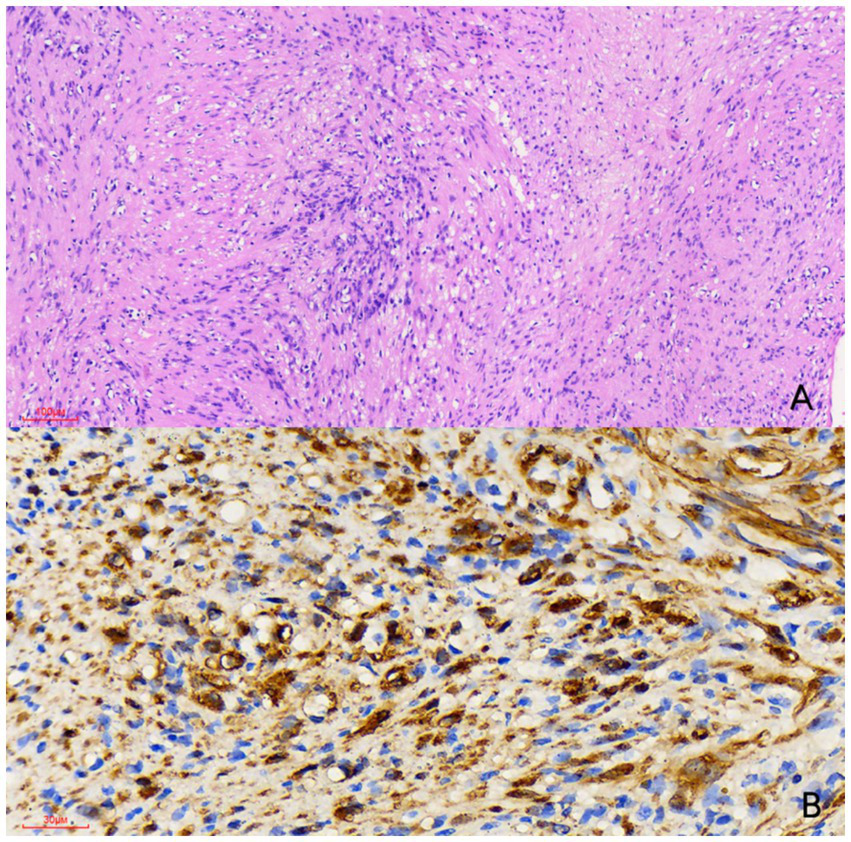

Figure 3

Histological examination [(A) hematoxylin and eosin stain, × 100] reveals a spindle cell tumor featuring a biphasic pattern with hypercellular and hypocellular myxoid areas (Antoni A and Antoni B regions). Immunohistochemical examination [(B) × 400] showed that the tumor cells were strongly positive for S-100 protein. Therefore, the nodule was diagnosed as a schwannoma.

Two months later, the patient’s symptoms significantly improved with no further fever. CTE on 22 July 2024, showed unchanged thickening and coarsening of the bowel walls, multiple full mesenteric lymph nodes, and a persistent cystic-solid nodule near the left common iliac artery, potentially a schwannoma. Enhanced MRI on 25 July 2024, confirmed these findings, with the nodule resembling an enlarged necrotic lymph node (Figure 2). Due to the unclear pathological diagnosis, tuberculosis, lymphoma, and other diseases could not be excluded, complicating the treatment of Crohn’s disease with biologics or immunosuppressants. MDT discussion on 29 July 2024 recommended surgical resection over percutaneous biopsy due to potential risks and complications. Surgery revealed a hard, smooth nodule (3 × 3 cm) in the mesentery above the left iliac artery. Preliminary pathology suggested a spindle cell tumor, and immunohistochemistry on 8 August 2024, confirmed it as a schwannoma with the following features: CD117 (−), CD34 (−), DOG-1 (−), SMA (−), S-100 (+), Desmin (−), Ki67 (+ 1%), SDHB (+), EMA (−), and BRAF (−) (Figure 3). The patient recovered well after surgery and was initiated on ustekinumab therapy for Crohn’s disease. Follow-up evaluations at 6 months and 1 year revealed no signs of schwannoma recurrence, with slight improvement in Crohn’s disease compared to the pre-treatment status.